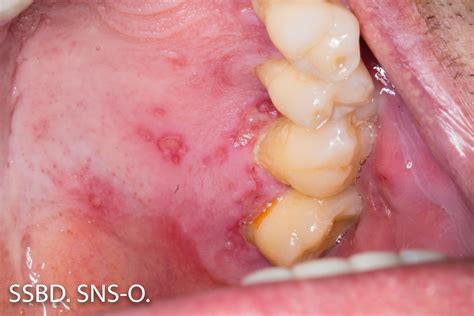

The virus responsible for oral outbreaks, Herpes Simplex Virus Type 1, is incredibly common. Once an individual is exposed, the virus typically remains dormant in the nerve ganglia, occasionally reactivating to cause lesions. While we often associate these lesions with the outer lip area, the virus can manifest as herpetic gingivostomatitis, a condition where the gums become inflamed, painful, and prone to bleeding. This is particularly common during a primary infection, which is the very first time the body encounters the virus.

In many cases, the interplay between herpes and gums is characterized by a sudden onset of symptoms. Unlike a standard canker sore, which usually appears as a single ulcer on the soft tissue inside the cheek, herpetic lesions often appear in clusters. When these clusters develop along the gumline, they can make routine hygiene like brushing extremely painful, leading to a temporary decline in oral health if not managed correctly.

• Small, fluid-filled blisters: These can rupture, forming small, painful ulcers on the gingiva.

Appearance Clustered blisters/ulcers Generalized swelling/redness